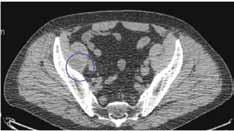

Val av operationsmetod vid cervikal och baso cervikal höftfraktur.

Svar: Odislocerade cervikala frakturer

Gruppen odislocerade frakturer innefattar grupp 1 och 2 enligt Gardens klassifikation. Osteosyntes förordas internationellt i alla ål dersgrupper.

Dislocerade cervikala frakturer

Numera rekommenderas protes, hel- eller halv-, till alla Garden 3-4. Protes har visat sig signifikant bättre vad gäller funktion, smärta och livskvalitet och de som läker efter osteo syntes blir inte bättre än de protesbehandlade (ref: NOA-studiens 10-årsresultat; Leonards son et al. JBJS Br).

Osteosyntes har också sin plats hos de med dislocerad fraktur och biologisk ålder under c:a 65 års ålder men här finns inga säkra riktlinjer.

Primär artroplastik rekommenderas dessutom oavsett patientens ålder i följande fall:

1. vid reumatoid artrit

2. vid cervikalfraktur sekundär till malignitet eller annan destruktion av höftleden.

3. vid cervikal fraktur där diagnosen fördröjts mer än en vecka.

4. vid samtidig artros i den frakturerade höftleden.

Basocervikala frakturer

Ur stabilitetssynpunkt behöver dessa frakturer vanligtvis opereras som trokantära frakturer med glidskruv och kortare platta.